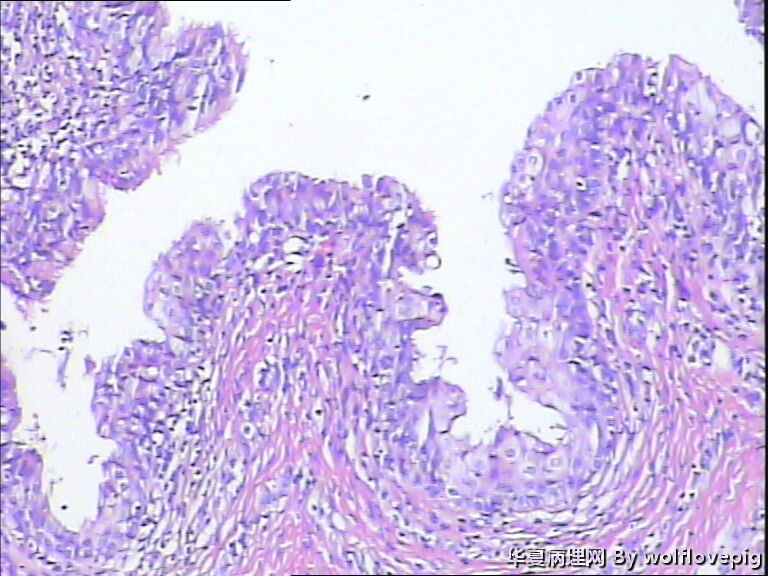

31y,阴蒂附近囊肿2.0*1.5cm

外阴最常见的囊肿是前庭大腺囊肿,囊肿一般衬以移行上皮,常伴有非角化性鳞状化生,也有的呈扁平或立方状,囊肿周边附近可以见到黏液腺体。

此例有点特殊,看到一些纤毛柱状上皮被覆,称为纤毛囊肿,属于前庭大腺囊肿的特殊改变。

前庭大腺囊肿位于外阴后半部,而此例位于阴蒂附近。

泌尿生殖窦起源的外阴囊肿(粘液性和纤毛囊肿)

1,多见于21-30及31-40的多产妇女,病变多位于外阴前庭。

2,组织学上,粘液性囊肿含有与宫颈内膜或阴道腺病一样的粘液性上皮内衬,少数情况下可出现鳞状上皮化生。也有报道有些病例出现纤毛细胞,可以与粘液上皮混合存在。